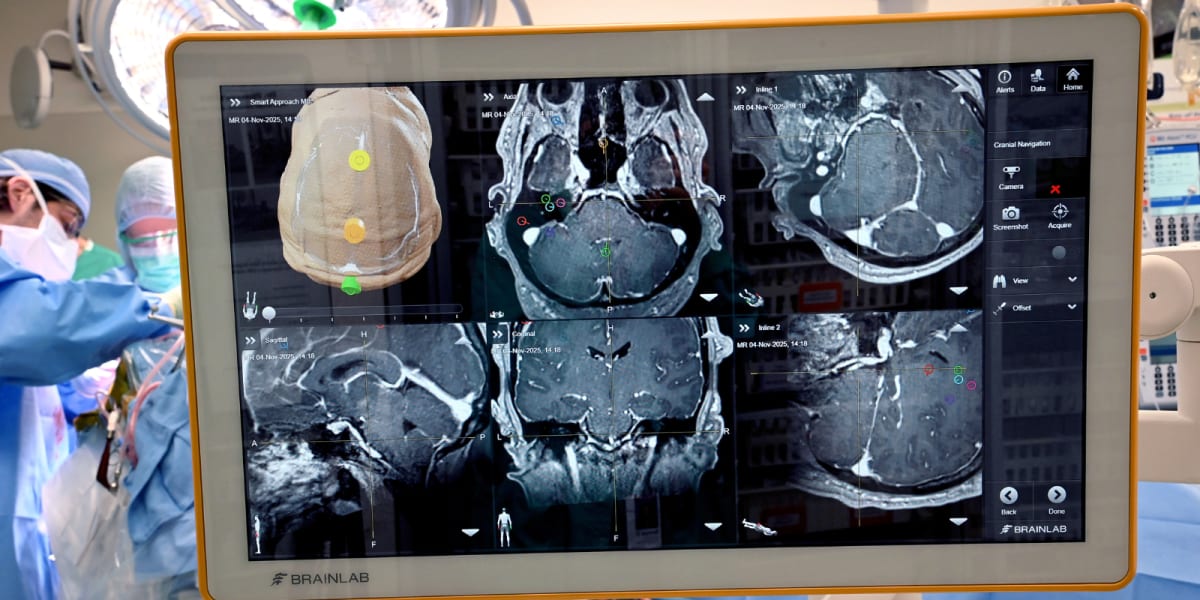

Neurosurgeons at UCHealth University of Colorado Hospital just completed the state's first brain-computer interface surgery on a 41-year-old patient paralyzed from the neck down after an accident. The tiny implanted device reads his brain's electrical signals and translates his thoughts into real-world actions, like controlling a robotic arm or using a computer.

But this surgery goes beyond previous brain implants in a remarkable way. The team placed the device in higher-level brain areas that control both movement and sensation, making them among the first in the world to attempt this approach.